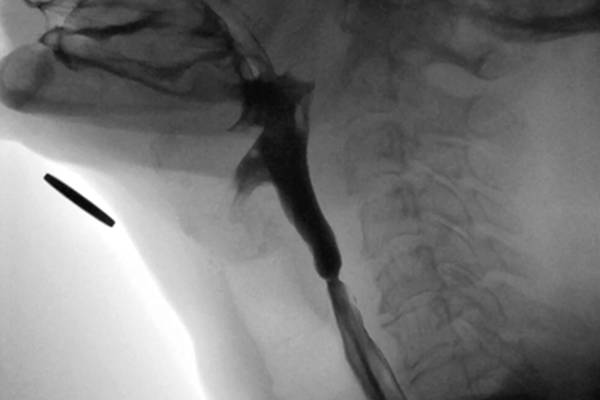

Muscle tension dysphagia: an underdiagnosed problem

Dysphagia in complex laryngology – maintaining the balance